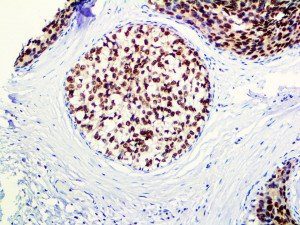

It is the ICU physician who is most likely to witness one of the deadliest manifestations of the abnormal immunological response, the cytokine storm syndrome (CSS). This response is also referred to by some as the cytokine release syndrome (CRS). CSS is characterized by continuous activation and expansion of macrophage and lymphocyte populations, which secrete large amounts of cytokines, causing the cytokine storm. This massive cytokine release is akin to hemophagocytic lymphohistiocytosis (HLH) disease, a syndrome characterized by initial unchecked and persistent activation of cytotoxic T lymphocytes and NK cells.

Clinical and laboratory manifestations of HLH include fever, enlarged liver and/or spleen, neurologic dysfunction, coagulopathy, liver dysfunction, cytopenias (i.e., low levels of erythrocytes, leukocytes, and/or platelets), hypertriglyceridemia, hyperferritinemia, hemophagocytosis, and eventually diminished NK cell activity as the immune system becomes progressively paralyzed. HLH can be familial (primary HLH) or secondary to another disease process (sHLH), such as rheumatic disease, in which it is referred to as macrophage activation syndrome (MAS, characterized by elevated ferritin).